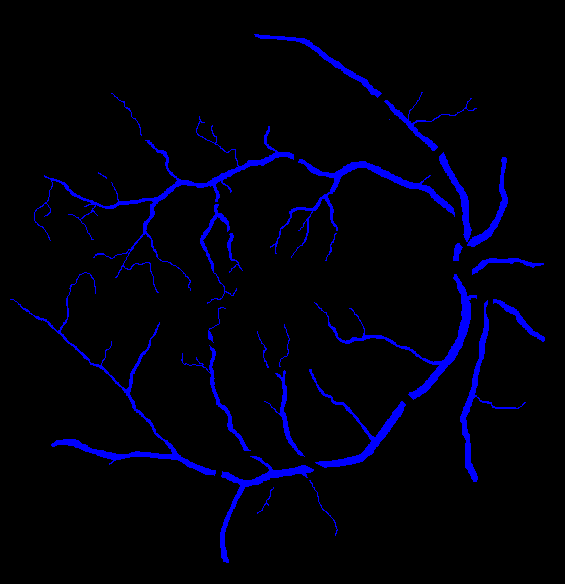

The visual differentiation between arteries and veins can be difficult in some cases, like small vessels with poor contrast and not clearly connected to a specific arterial or venular tree. These cases can be identified with certainty as vessels, but their classification into arteries and veins is uncertain, even for an expert. Additionally, it is common to find crossings between arteries and veins in the retina. Thus, although for these positions either the artery or the vein is above the other, these pixels can be regarded as simultaneously belonging to both types of vessels. This allows to account for continuous arterial and venular trees regardless of crossings below the other one. The identification of these two special situations (uncertain vessels, and vessel crossings) is common in manually annotated retinal vessel classification datasets [38, 42, 43, 44]. Figure 1 shows an example of a ground truth image from the RITE dataset labelled this way, along with its decomposition into arteries, veins, crossings and uncertain vessels.

Also, an example of a retinography and its corresponding vasculature segmentation and A/V classification ground truths is depicted in Figure 6.

In order to train the networks following the traditional and MS approaches, the ground truth images from the RITE dataset are adapted, in each case, to the output of the network. In the traditional approach, each pixel of the ground truth is assigned to either background, artery, vein or “uncertain or crossing” class, which comprises both uncertain vessels and crossings. The resulting ground truth is a grayscale image in which each pixel has a numeric label of the class to which it belongs. On the other hand, in the MS approach, each pixel is assigned to any number of the following classes: artery, vein and vessel. In this case, crossings belong to the three classes, and uncertain vessels belong only to the “vessel” class. Background pixels are not assigned to any class. The resulting ground truth is an RGB image in which each channel contains a manual segmentation mask of one of the aforementioned structures. An example of a RITE ground truth adapted to both the traditional and the MS approaches can be found in Figure 7.